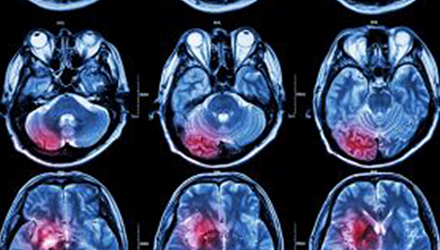

在這項研究中,研究人員使用功能核磁共振成像(fMRI)觀察大腦中血液含氧量的變化。研究人員首先研究了耳鳴患者和無耳鳴者的大腦活動,其目的是比較兩組受試者大腦處理情緒的方式。

在功能磁共振成像檢查中,受試者分別聽30種“愉悅”的聲音、30種“不愉快”的聲音和30種“中性”的聲音。這些聲音包括小孩咯咯笑,嬰兒啼哭,以及熱水壺燒開的聲音。

功能磁共振成像的結果顯示,當暴露于情緒性聲音下,耳鳴患者大腦不同區域的活動比沒有耳鳴者的活動更強烈。接著,研究人員進行了更深入的研究:耳鳴患者的大腦活躍性和耳鳴嚴重程度的關系。

耳鳴嚴重程度和大腦額葉的關系

調查結束后,再進行功能核磁共振成像檢查。第二輪功能核磁共振成像顯示,那些耳鳴較輕的患者實際上使用了大腦不同的區域來處理情緒信息。

傳統觀點認為,大腦中的扁桃體是處理情緒的關鍵,但此次研究發現,那些不被耳鳴困擾的患者實際上使用更多大腦額葉來處理情緒。這類患者額葉活動更顯著的原因是,額葉通常更多地用于注意力、計劃和沖動的控制。